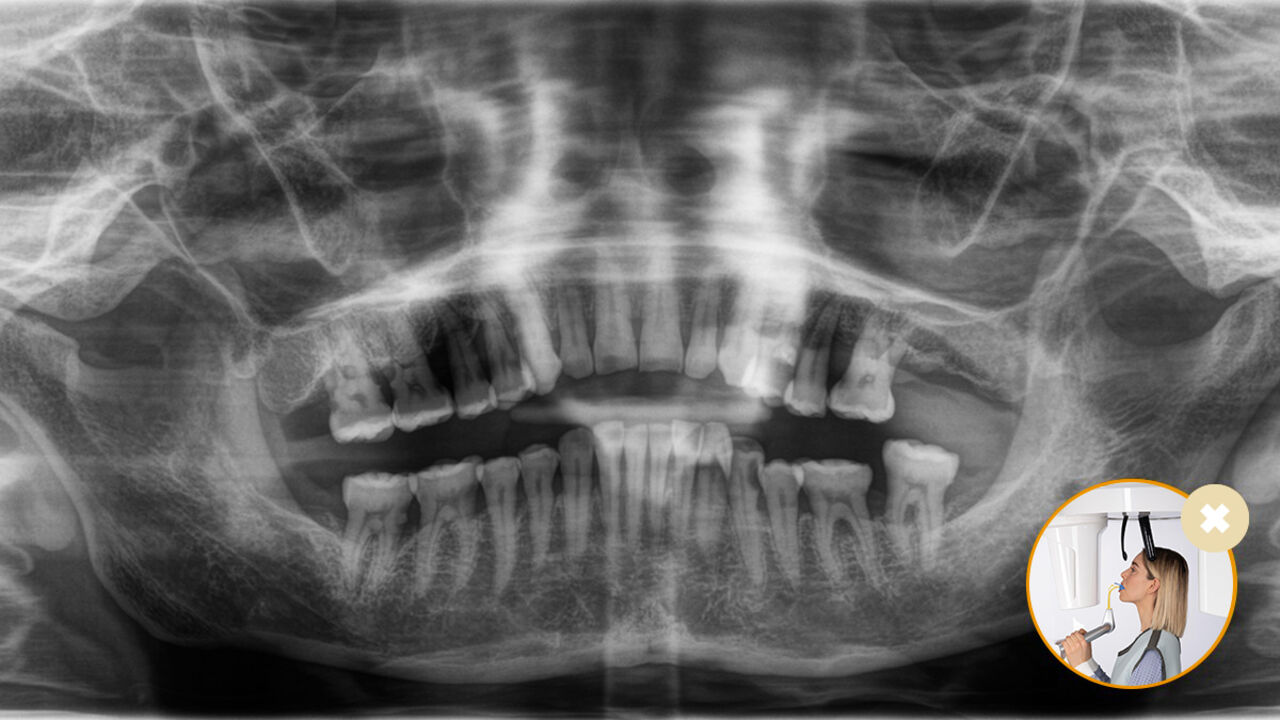

Le positionnement correct du patient permet d’obtenir une qualité d’image élevée pour un diagnostic précis et améliore l’expérience du patient.

Voici notre concept de positionnement du patient et d’imagerie radiographique en 10 points. Deux éléments essentiels : une qualité d’image élevée et le confort du patient et de l’assistant.